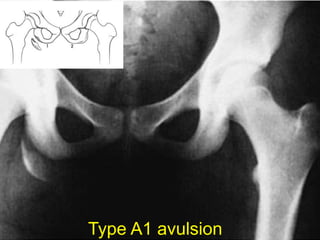

Tile A1

Type A1 avulsion